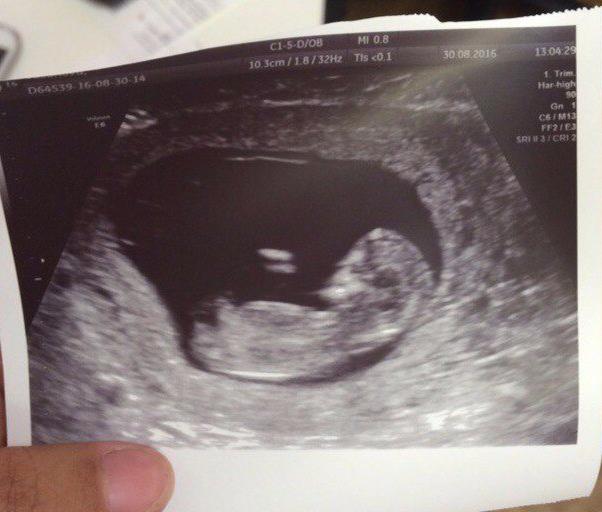

Завтра 12 недель 🙏

Сегодня ходили на первое узи, послушали сердечко..в первую б я ничего не поняла, а тут так хорошо все видно :) прям настоящий человечек :) на фото, правда, как-то пол лица обрублено Оо